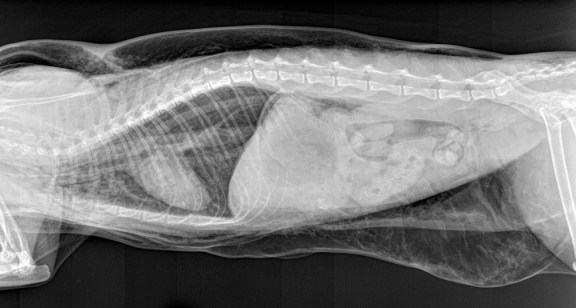

Signalement: Chatte stérilisée de 6 ans.

Histoire clinique: Présentée en dyspnée 12 heures après un détartrage de routine.

Y a t il eu rupture de la trachée lors de l’intubation??

Et bien… la réponse est oui ! (voir le billet sur la suite pour plus d’infos)